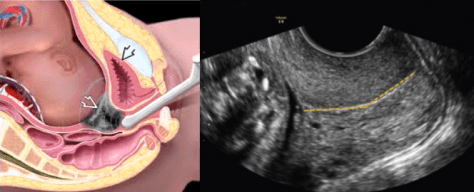

Цевікометрія

Цевікометрія (вимірювання довжини шийки матки).

Шийка матки утримує плід в матці протягом всієї вагітності. Іноді тонус м’язів шийки матки слабшає передчасно, при цьому вона починає скорочуватися і розкриватися. Щоб вчасно виявити цей процес і запобігти передчасному народженні дитини необхідно вимірювати довжину шийки матки.

Ультразвукове дослідження шийки матки застосовується для прогнозування передчасних пологів. Чим коротше довжина шийки матки, тим вище загроза передчасного переривання вагітності. Короткою вважається шийка матки довжиною менше 25 мм.

Довжина шийки матки може визначатися при зовнішньому УЗД через передню черевну стінку (трансабдоминальне УЗД) або через промежину і статеві губи (трансперінеальне УЗД).

Однак для більш точного вимірювання довжини шийки матки проводиться трансвагінальне дослідження (через піхву), при якому буде отримано більш чітке зображення шийки матки.

При проведенні трансвагінального УЗД ускладнень не виникає. Трансвагинальное УЗД є безпечним методом дослідження як для самої жінки, так і для плода.